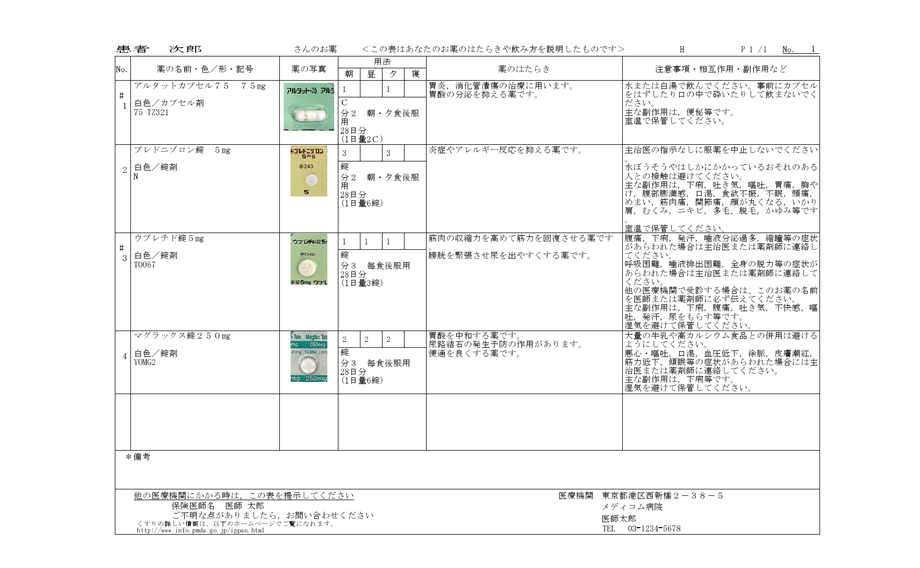

複数の医療機関・薬局間での情報の共有が進むことで、重複投薬防止等が可能となります。また、統一フォーマットでのやり取りにすることで、疑義照会や調剤情報の確認等の負担が軽減されます。

直近の処方情報とともに、オンライン資格確認等システムから入手できる薬剤情報等を参照することにより、質の高い医療の提供をすることができます。